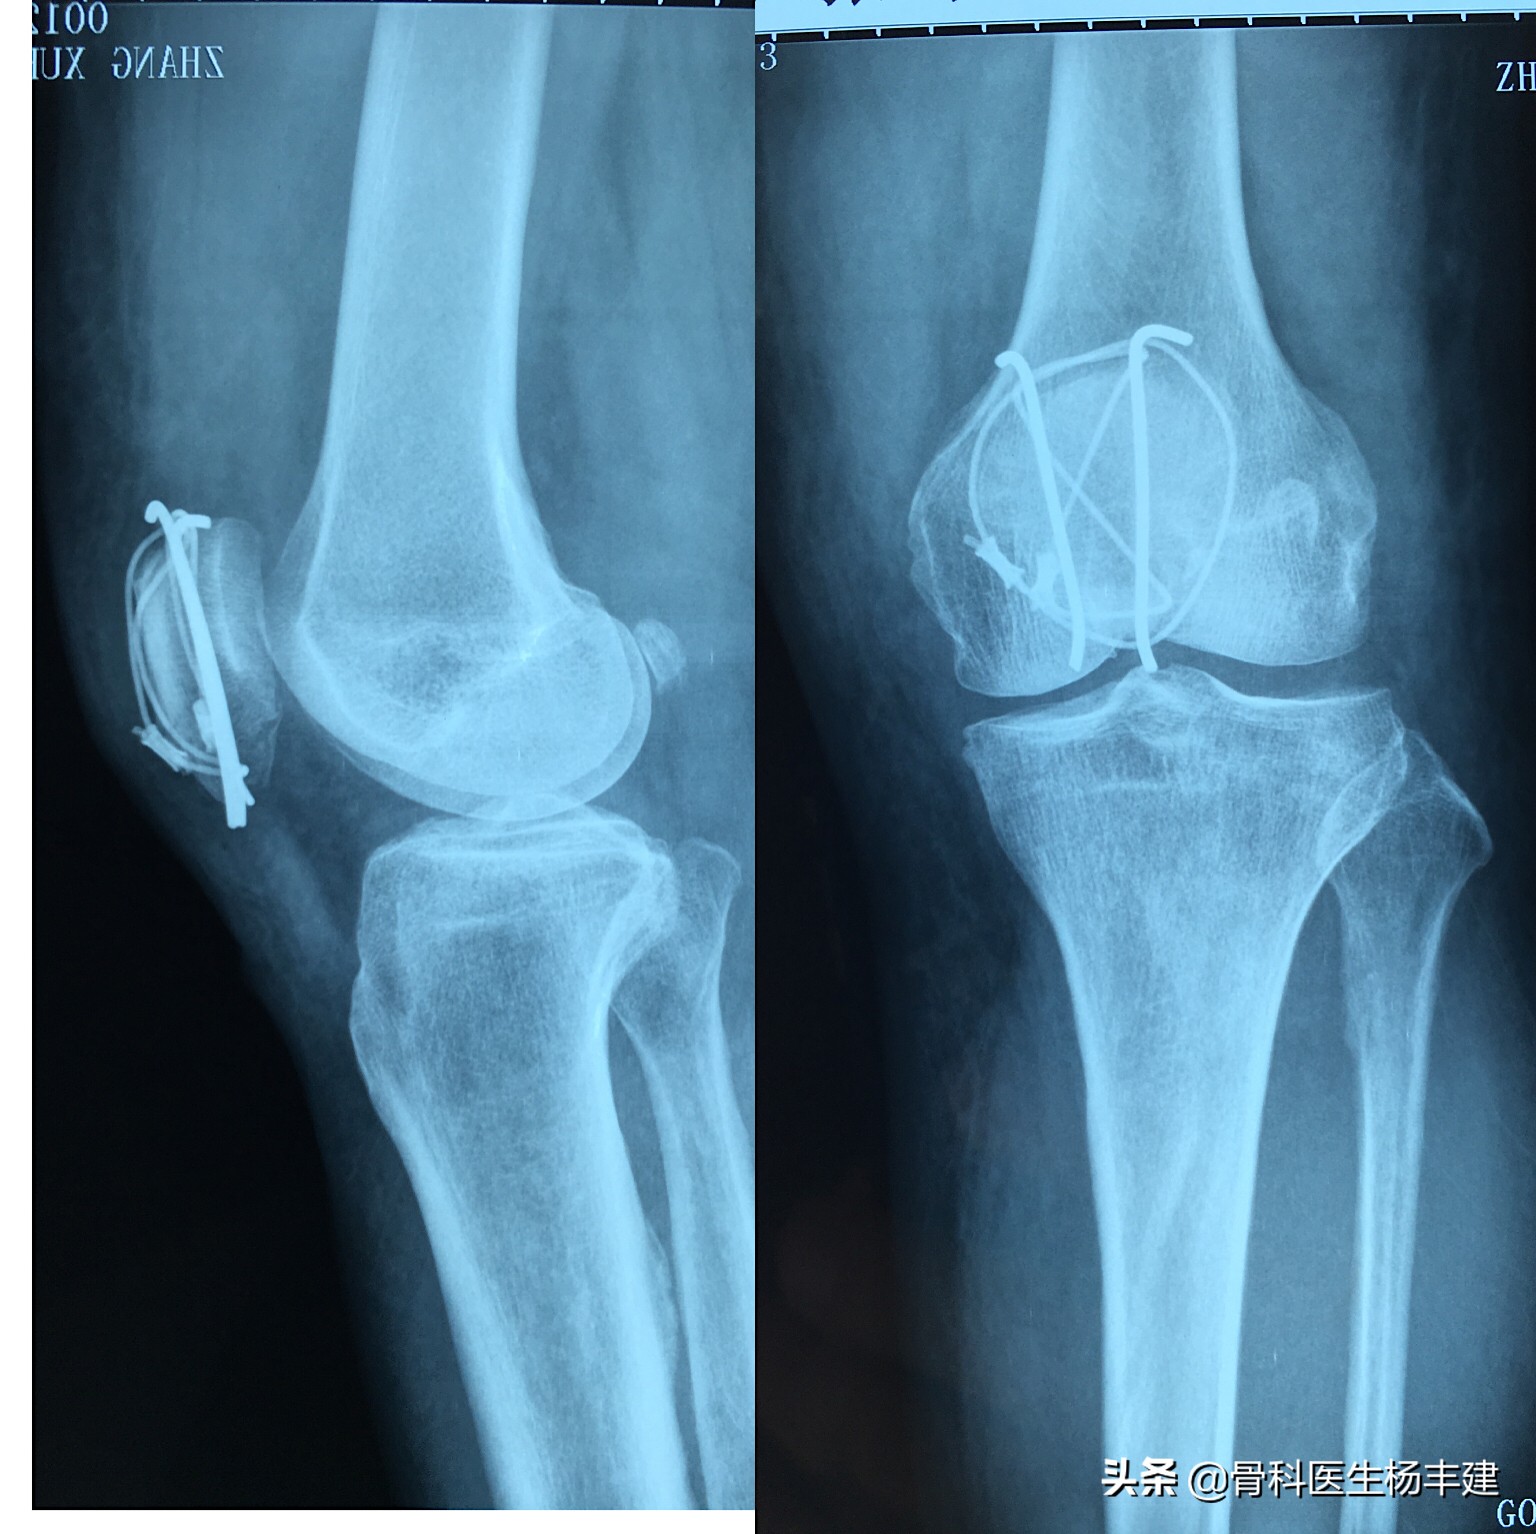

使用克氏针和钢丝固定的髌骨骨折